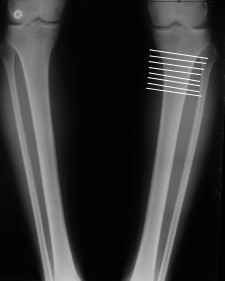

Картинки - в приложении.Будут вопросы - готов ответить.

Ещё картинка - схема. Хотя у Соломина всё написано.

Мне представляется оптимальным на уровне 3-4 линии (т.е. как раз посредине отмеченной зоны). Если рассчимтываешь делать медиализацию, то параллельно суставной поверхности, иначе просто не сдвинешь без джистракции - отломки зацепятся. Если без медиализации - то вообще не имеет значения.